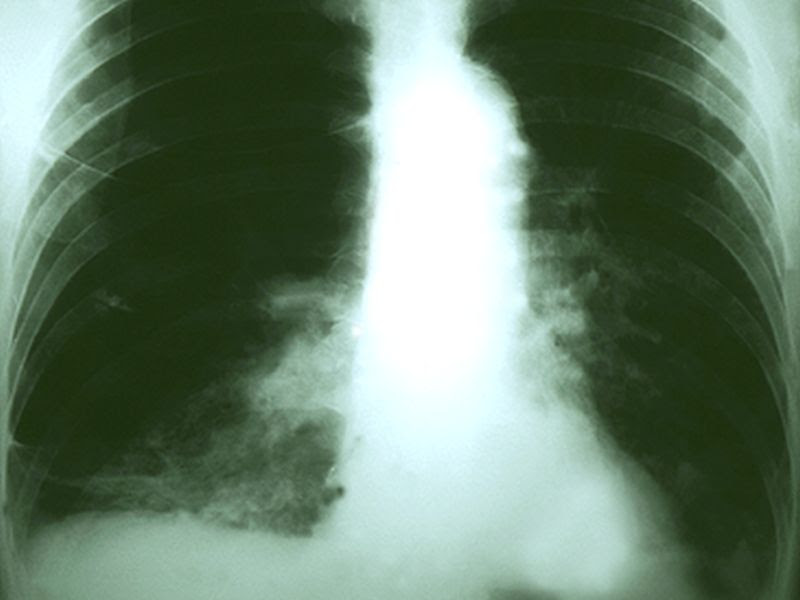

Do Too Many Lung Cancer Patients Miss Out on Surgery?

Lung Cancer